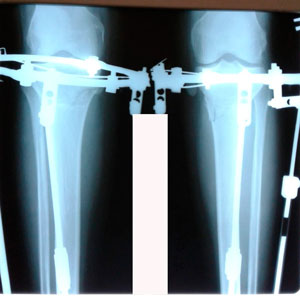

Исходник - 42 года.

Дата операции - 27.05.2020

Красивые ноги получились!